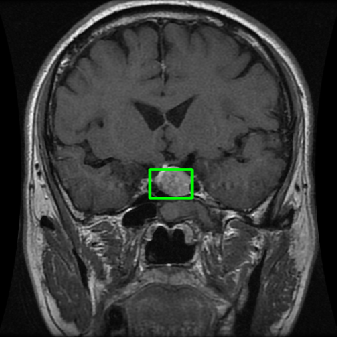

From the above discussions, we have discovered the significant potential of applying Retinex theory to image segmentation and explored its fundamental differences from traditional models. Traditional image segmentation models typically focus on the impact of intensity information on the segmentation results. Therefore, when faced with complex segmentation scenarios, the segmentation results are often affected by lighting, artifacts, and unclear boundaries in the image. As shown in Fig. 1, we present the results of the classical local model LIF [ZHANG20101199] for segmenting brain tumor images along with surrounding tissue edema. The irregular ring-like enhancement caused by the edematous tissue leads to irregular boundaries and low contrast in the images. Consequently, the LIF model can only identify the central necrotic and liquefied regions of the tumor, failing to detect the boundaries and becoming trapped in local minima. In this paper, we draw inspiration from the Retinex theory, which is widely applied in the field of image enhancement. According to Retinex theory, the reflectance component characterizes the intrinsic structural properties of the observed image and preserves texture information independent of illumination variations. By integrating this reflectance component into the level set framework, our model achieves robust segmentation of medical images even under severe intensity inhomogeneity. In addition, a linearized Structural-Prior is proposed to restore intensity consistency and capture local geometric features, thereby improving boundary localization in complex or blurred regions. Furthermore, a relaxed binary level set representation is employed to enhance robustness against noise and to enable accurate tracking of complex contours. Based on these innovations, we propose a novel variational reflectance-based level set model (RefLSM) that simultaneously corrects bias fields and performs segmentation. Experimental results demonstrate that RefLSM significantly outperforms conventional level set methods in both segmentation accuracy and robustness. We present the results of our model segmenting the two brain tumor images mentioned above in Fig. 2.

To address the challenge of segmenting images with severe intensity inhomogeneity, we propose a linearized structural prior that directly operates on the reflectance component . Reflectance-based structural information is more robust to illumination variations and bias field distortions, helping preserve weak edges and subtle anatomical boundaries. As shown in Fig. 2, our method can accurately delineate tumor boundaries and surrounding edema even under severe inhomogeneity, where traditional intensity-based models often fail. The proposed prior aligns smoothed reflectance gradients with data-driven directions, enhancing inter-region contrast, preserving weak edges, and stabilizing the evolution of . Formally, we define the linear structure operator as the gradient field of the smoothed reflectance:

4.2 Comparison with brain tumor MR images segmentation

Brain tumor MRI images represent a critical challenge within the field of medical image analysis, making them a focal point of our research. Various level set models for image segmentation have been applied to brain tumor MRI images, and it is essential to consider the unique characteristics of these images. To validate the excellent performance of the RefLSM, we conduct segmentation comparison experiments on brain MR images and compute the Dice coefficient and Precision values for all evaluated models.

Fig. 4 displays the visual comparison results for segmenting eight brain tumor MR images between the RefLSM and three representative models: the RESLS [8765635], ALF[MA2019201], and L1 model[LIU2019193]. These images exhibit severe intensity inhomogeneity and noise attributable to inconsistent bias field and imaging equipment. The initial level set function (LSF) initialization was consistent across all models, as shown in Fig. 4 (a), which illustrates the initial placement of the zero level contour. For visual clarity, we included the ground truth in Fig. 4 (f). The segmentation outcomes from the RESLS, ALF, and L1 methods are presented in Fig. 4 (b), (c), and (d), respectively.

It is evident from the first and last columns of Fig. 4 (b) that the ALF model tends to become trapped in local minima under severe intensity inhomogeneity. Furthermore, segmentation results presented in the columns 1-4 of Fig. 4 (b) and (c) reveal that both the ALF and L1 models mistakenly segment small isolated or irrelevant regions due to the effects of irregular intensity patterns. Additionally, when weak boundaries are present, as seen in the 1st and 3rd columns of Fig. 4, the RESLS, ALF, and L1 methods fail to accurately identify object boundaries. Consequently, the zero level contours of these models deviate significantly from the objects throughout the level set evolution, causing drastic misalignment after further iterations.

In stark contrast, our proposed method exhibits greater robustness against images exhibiting severe intensity inhomogeneity and weak boundaries. The proposed prior constraint term effectively corrects for intensity inhomogeneity, while the proposed binary level set adeptly reduces noise during the segmentation process.

Overall, these findings demonstrate that the segmentation outcomes produced by our model are more accurate. Besides visual assessment, we calculate the Dice and Precision values of evaluated models for brain tumor segmentation in table 1. Based on these results, we draw a boxplot with scatterplot overlay, as shown in Fig. 6, which displays the data distribution and facilitates comparison of different models’ performance across various brain tumor MR images. We analyze the maximum, median, and minimum, which correspond to the best, median segmentation results, and worst segmentation results, respectively. It is clear that the RefLSM achieves more accurate segmentation results compared to the other models. Moreover, the smaller range of the RefLSM in the boxplot indicates robustness and stability to different images of the brain tumor.